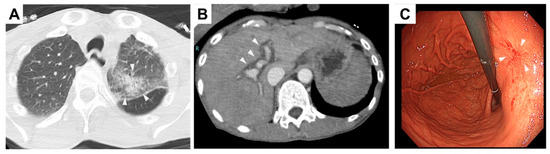

2. Case Presentation